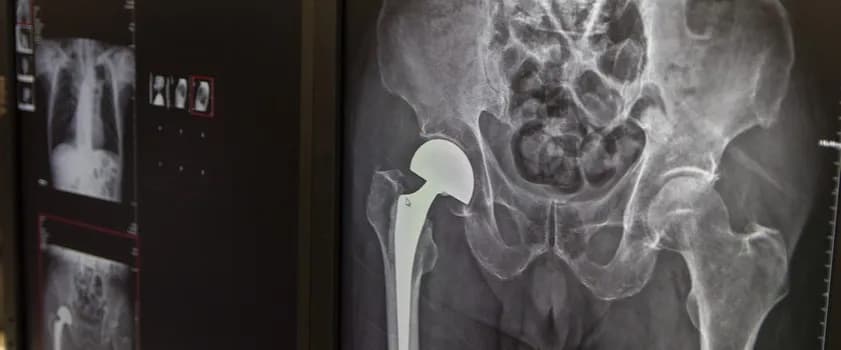

Aby zdiagnozować hiperostozę czołową, lekarze stosują różne metody diagnostyczne, które pomagają ocenić stan kości czołowej. Najczęściej wykorzystywane są zdjęcia rentgenowskie oraz tomografia komputerowa (CT). Te techniki obrazowania pozwalają na dokładne zobrazowanie struktury kości i wykrycie wszelkich nieprawidłowości. Dzięki tym badaniom możliwe jest zidentyfikowanie obszarów, w których występuje nadmierny wzrost kości, co jest kluczowe dla postawienia diagnozy. Właściwa ocena wyników badań jest niezbędna do dalszego postępowania medycznego.

| Metoda | Efektywność | Typowe zastosowanie |

| Zdjęcia rentgenowskie | Dobre | Wstępna ocena struktury kości |

| Tomografia komputerowa (CT) | Bardzo dobra | Szczegółowa analiza kości czołowej |